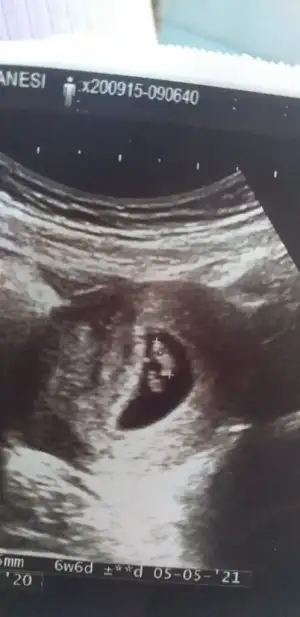

Kızlar tahmin alabilirmiyim bende

• IMG-20200915-WA0004.webp

IMG-20200915-WA0004.webp

21,4 KB · Görüntüleme: 86